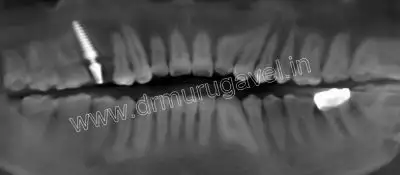

After implant placement

X-ray

dental implant cost india